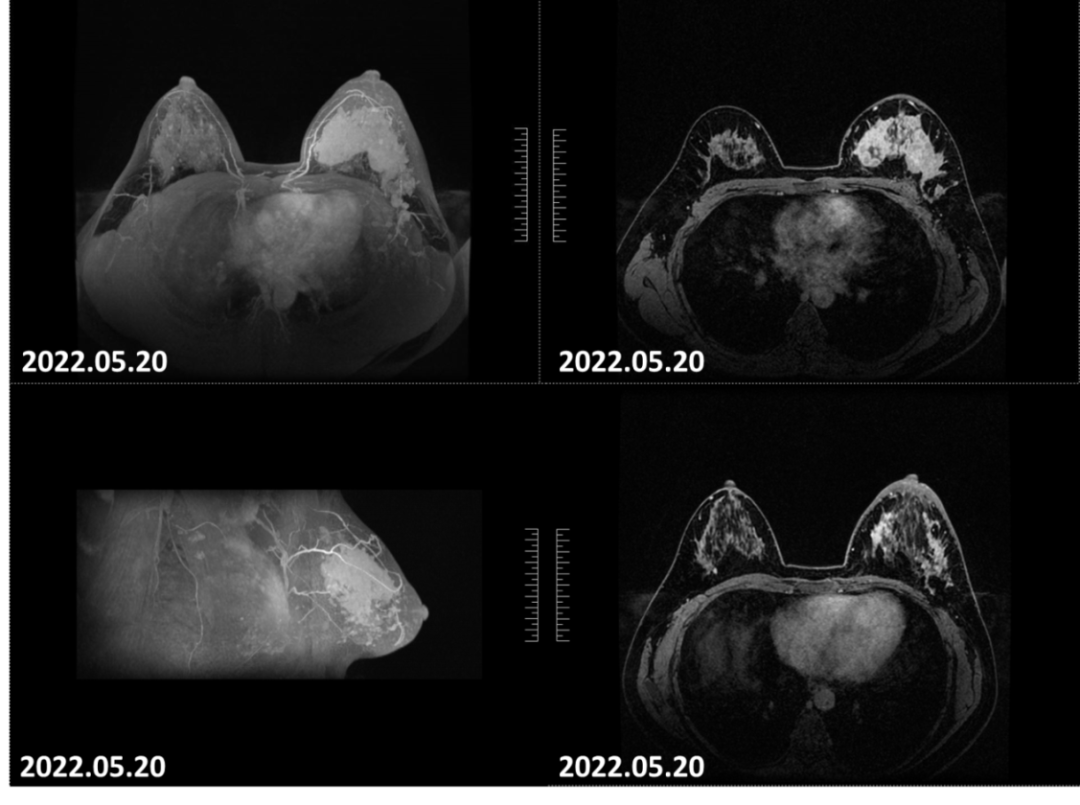

2022-05-20乳腺MRI报告:双侧乳腺欠对称,左乳较大,左乳皮肤局限增厚,左乳上方象限病变可见明显强化,边界不清,大小约46mm×73mm×52mm(上下径×左右径×前后径),病变前缘距乳头约17mm,后缘距离胸壁约8mm。左侧腋窝淋巴结肿大,最大直径约13mm。

图1.患者入院乳腺磁共振可见左乳肿瘤病灶范围广、累及皮肤,符合炎性乳腺癌表现。

2022-07-08乳腺MRI报告:左乳上方象限病变可见明显强化,边界不清,大小约24mm×30mm×21mm(上下径×左右径×前后径),病变前缘距乳头约34mm,后缘距离胸壁约11mm。右乳约11点钟方向病变可见明显强化,边界不清,直径约9mm,病变前缘距乳头约50mm,后缘距离胸壁约32mm。左侧腋窝淋巴结肿大,最大直径约8mm。

图4.2疗程后患者左侧乳房肿物退缩明显,强化程度减低。

2022-08-20乳腺MRI报告:左乳上方可见点灶状强化,以左乳约3点钟方向稍明显,直径约4mm。大小约24mm×30mm×21mm(上下径×左右径×前后径),病变前缘距乳头约34mm,后缘距离胸壁约11mm。左侧腋窝淋巴结肿大,最大直径约7mm。

图6.4疗程后患者左乳肿物轮廓不明显,左乳肿物及左腋窝淋巴结均无明显增强。